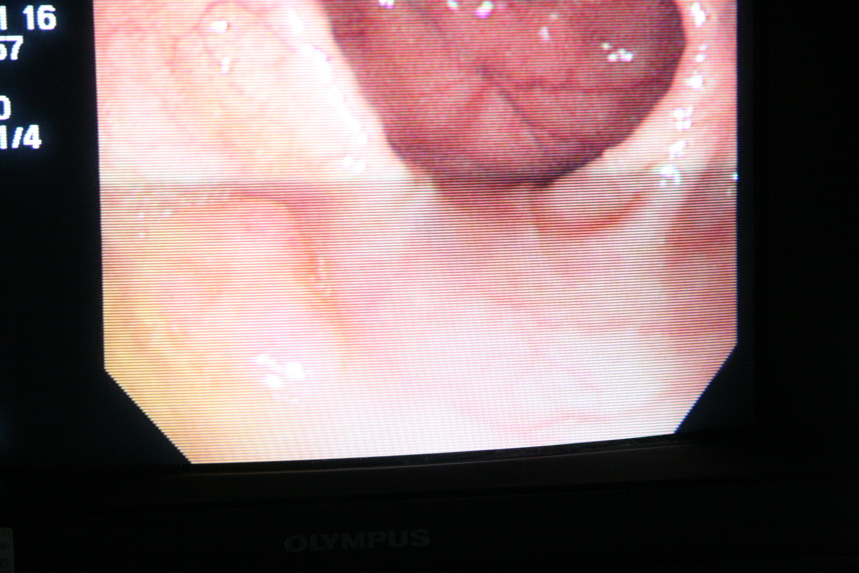

IMG_8650.JPG